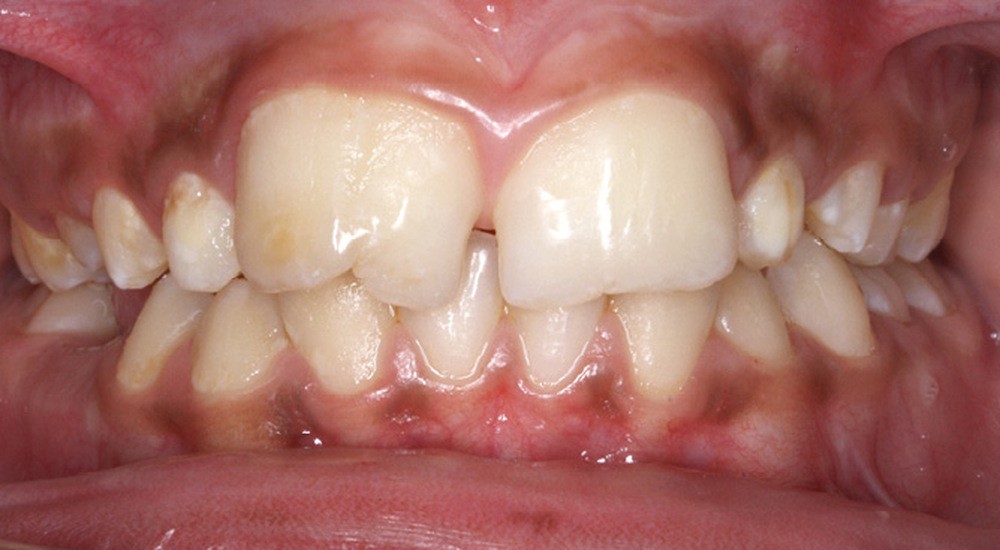

Antony, 11 ans se présente initialement pour une demande esthétique concernant ses deux incisives centrales qu’il trouve trop grosses (fig. 1a-c).

Le profil est convexe et associé à une inocclusion labiale au repos. Il s’agit d’une classe II squelettique sur un schéma facial normodivergent. Les rapports occlusaux sont de classe II bilatérale (complète au niveau molaire) avec des incisives inférieures vestibulo-versées. La 21 est géminée et la 11 vraisemblablement fusionnée avec un germe surnuméraire, sans altération de la formule dentaire. Du fait du diamètre mésiodistal fortement augmenté des incisives centrales, et du manque de place à l’arcade maxillaire qui en découle, les 12 et 22 sont en inversé d’occlusion en palato position. Les 53 et 63 sont persistantes sur l’arcade avec une inclusion en transposition incomplète de la 13, dont la cuspide se situe entre la racine de la 12 et celle de la 11 résorbée (fig. 1d-g).